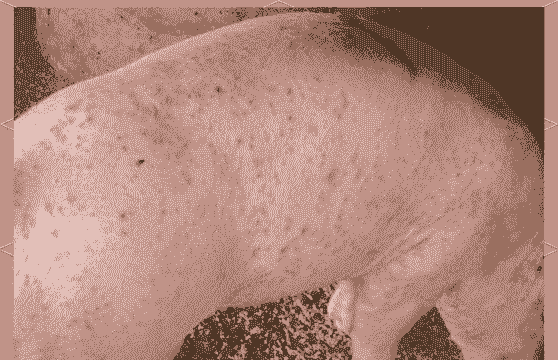

母猪产后全身红可能有多种原因,以下是一些可能的情况及建议:

附红细胞体病

附红细胞体病是一种热性、溶血性传染病,临床特征包括急性全身发红、发热、溶血等。建议使用维奥新奥兰的安瑞克+利瑞欣注射,第一天12小时1次,连用3-5天,并在饮水中添加一些药物和营养性物质。